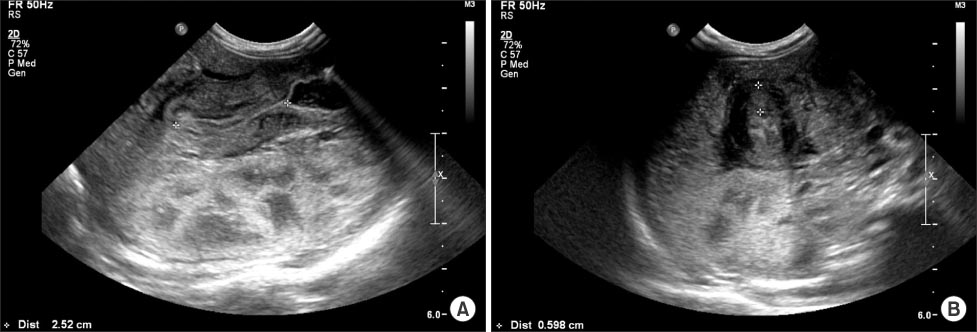

Fig. 1), and abdominal US revealed hypertrophied pyloric canal with 2.5 cm of length and 0.6 cm of thickness (

Fig. 2).

Fig. 2Abdominal ultrasonograms reveal 2.5 cm of pyloric length (A) and 0.6 cm of pyloric thickness (B).